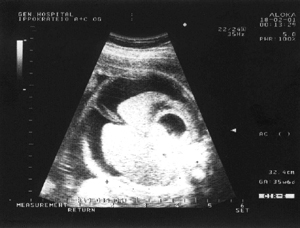

Εικόνα 1. Ενδοπεριτοναϊκο

ελέυθερο υγρό πριν την εμβυομετάγγιση

Στην παρούσα κύηση διαπιστώθηκε κατά τον υπερηχογραφικό έλεγχο του εμβρύου στην

30η εβδομάδα οίδημα του δέρματος μεγαλύτερο των 5 εκατοστών, πλευριτική και

περικαρδιακή συλλογή υγρού, ασκίτης (εικόνα 1), καθώς και οίδημα του πλακούντα

με τη μεγαλύτερη διάσταση άνω των 6cm. Τα ευρήματα ήταν συμβατά με τον ορισμό